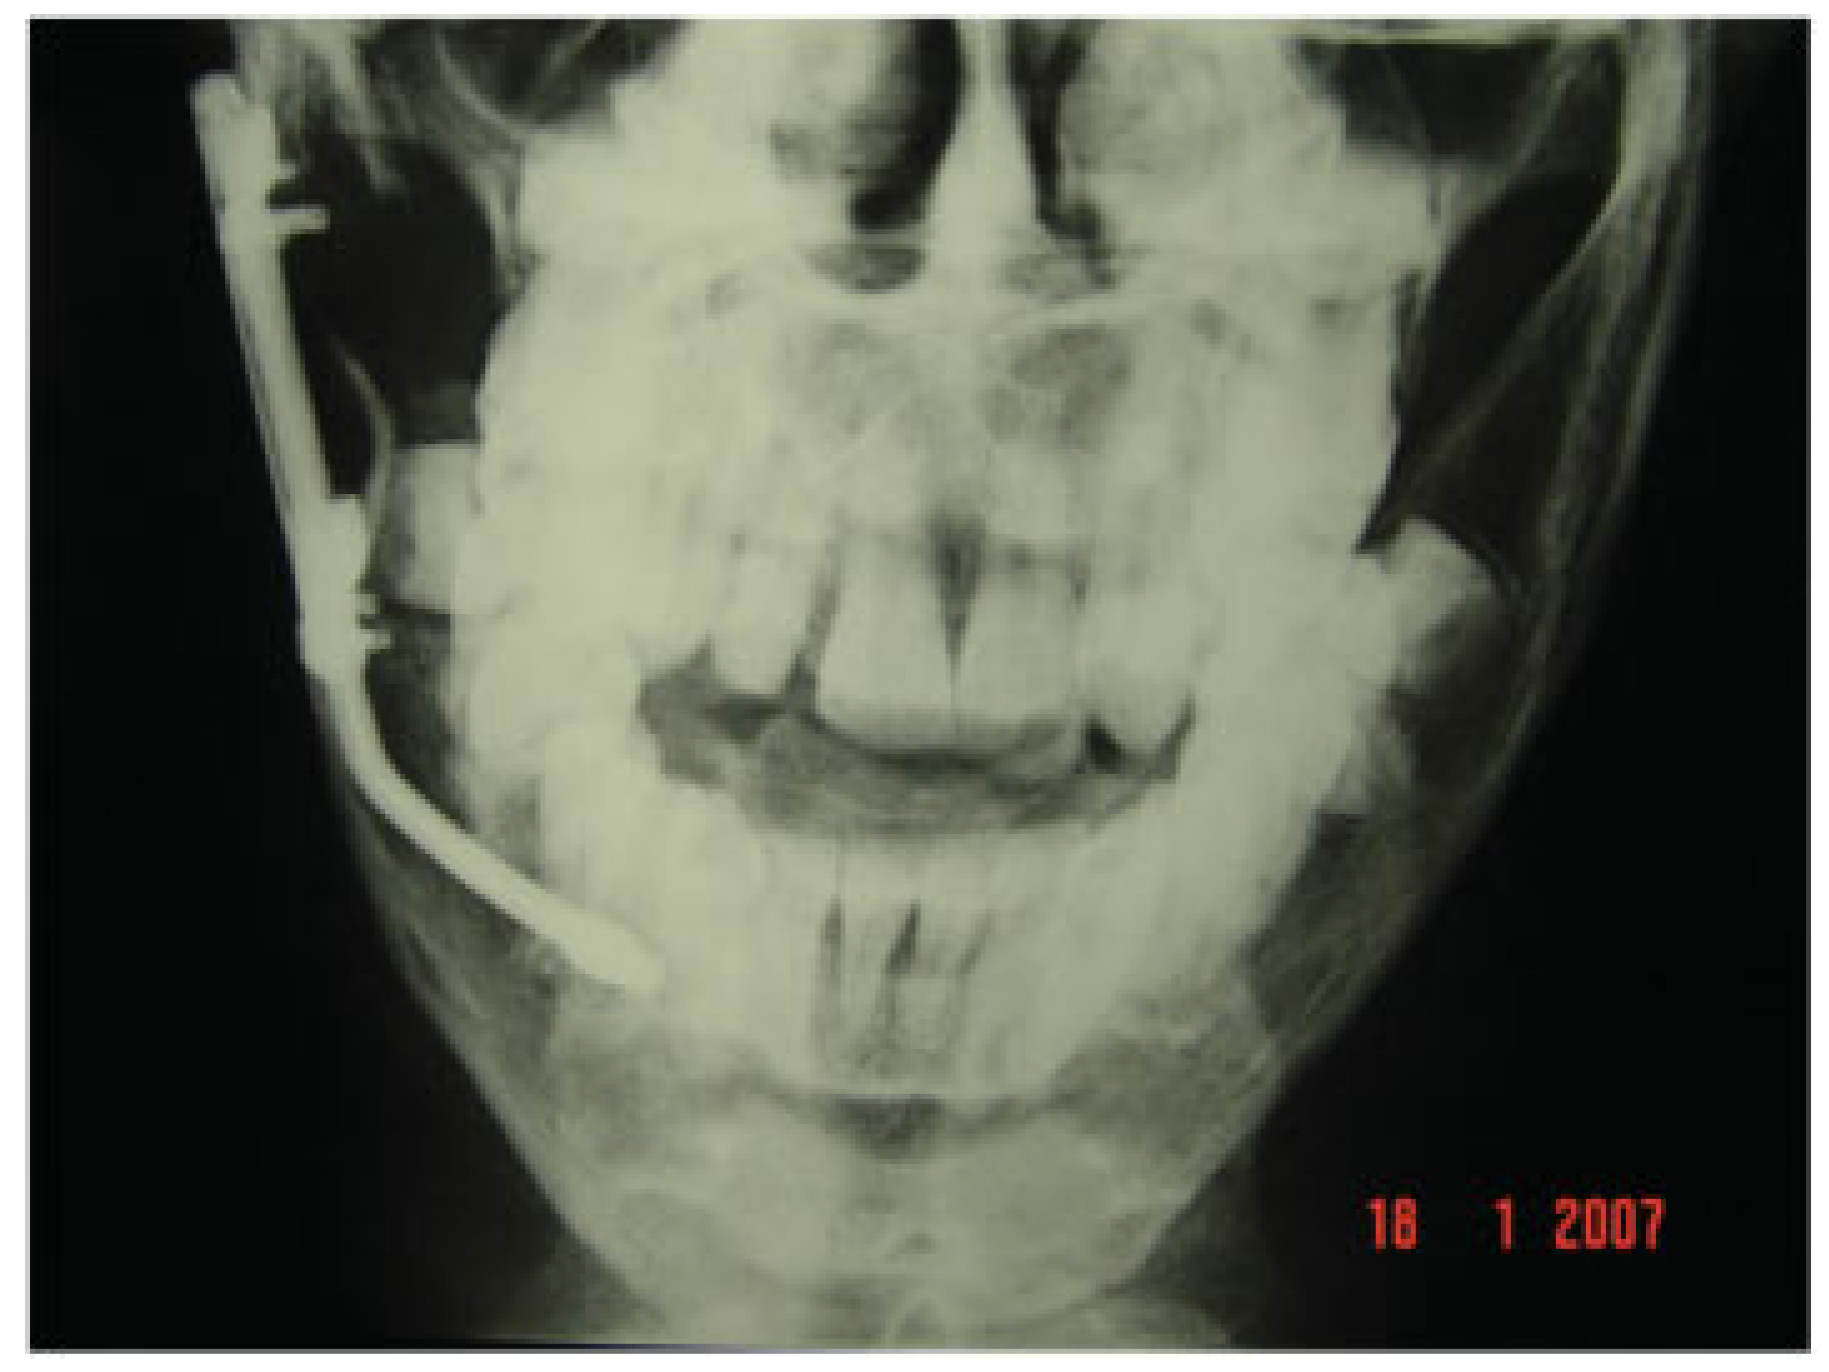

Figure 12. A posterior anterior radiograph showing that the screws used to secure the distractor plate were positioned to avoid damage to both the roots of the teeth and the developing tooth germs.

As the patient was young, it was deemed important to ensure that both the boney cuts and placement of the screws to secure the distractor plate were positioned to avoid damage to the roots of the teeth and developing tooth germs (Figure 12). A possible advantage of employing staggered buccal and lingual osteotomy cuts is that the width of the mandible is preserved as the callous is elongated as opposed to the formation of a narrow callous that might arise from a single vertical buccal-lingual osteotomy cut. However, the use of sagittal split osteotomy cuts results in a large surface area between the buccal and lingual plates for rapid healing to take place; consequently, distraction was started on the first postoperative day rather than on the fifth postoperative day with the standard vertical cut [5].